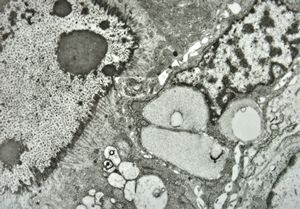

M,50y. | Pneumocystis carinii - lung